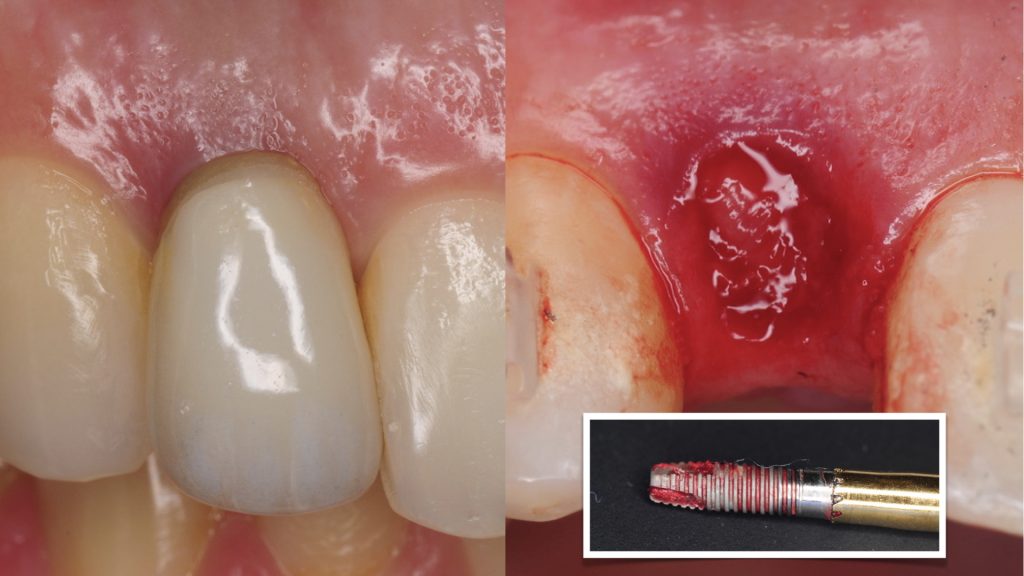

Explantation of an Anterior Implant with Excessive Buccal Inclination and Loss of Tissue

Staged management of a poorly positioned dental implant in the aesthetic zone with compromised results.